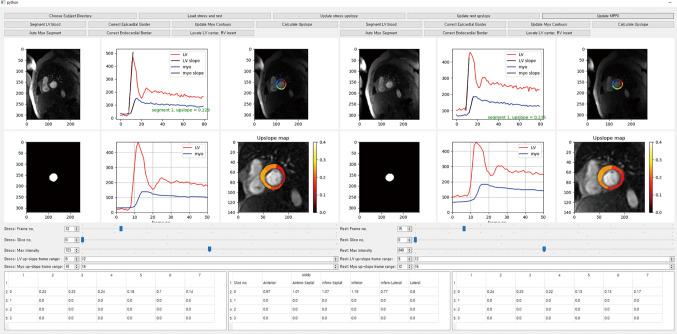

The method consisted of segmenting the myocardium in dynamic contrast-enhanced (DCE) myocardial perfusion MRI data using Monte Carlo dropout U-Net, dividing the myocardium into segments based on landmark localization with machine learning, and estimating the MPRI after the calculation of the left ventricular and myocardial contrast upslopes. The proposed method was compared with a reference method, which involved manual adjustments of the myocardial contours and upslope ranges.

In test subjects, MPRIs measured by the proposed technique correlated with those by the manual reference in segmental assessment [intraclass correlation coefficient (ICC) =0.75, 95% CI: 0.70-0.79, P<0.001]. The automatic and reference MPRI values showed a mean difference of -0.02 and 95% limits of agreement of (-0.86, 0.82).